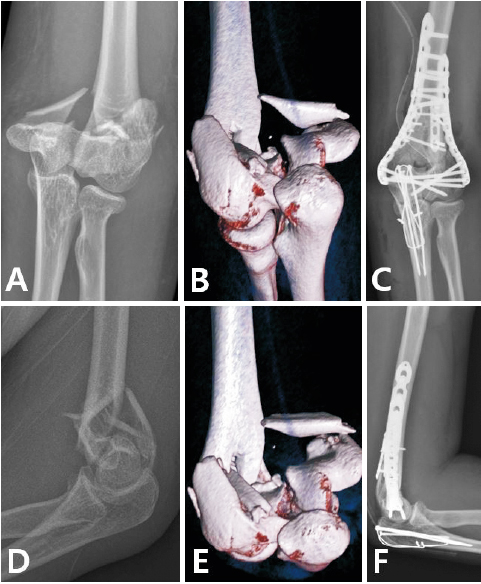

Fig. 2

Double plating of distal humerus fracture. (A, B) Preoperative X-ray. (C, D) Double plating at medial and lateral column. (E, F) Postoperative X-ray.